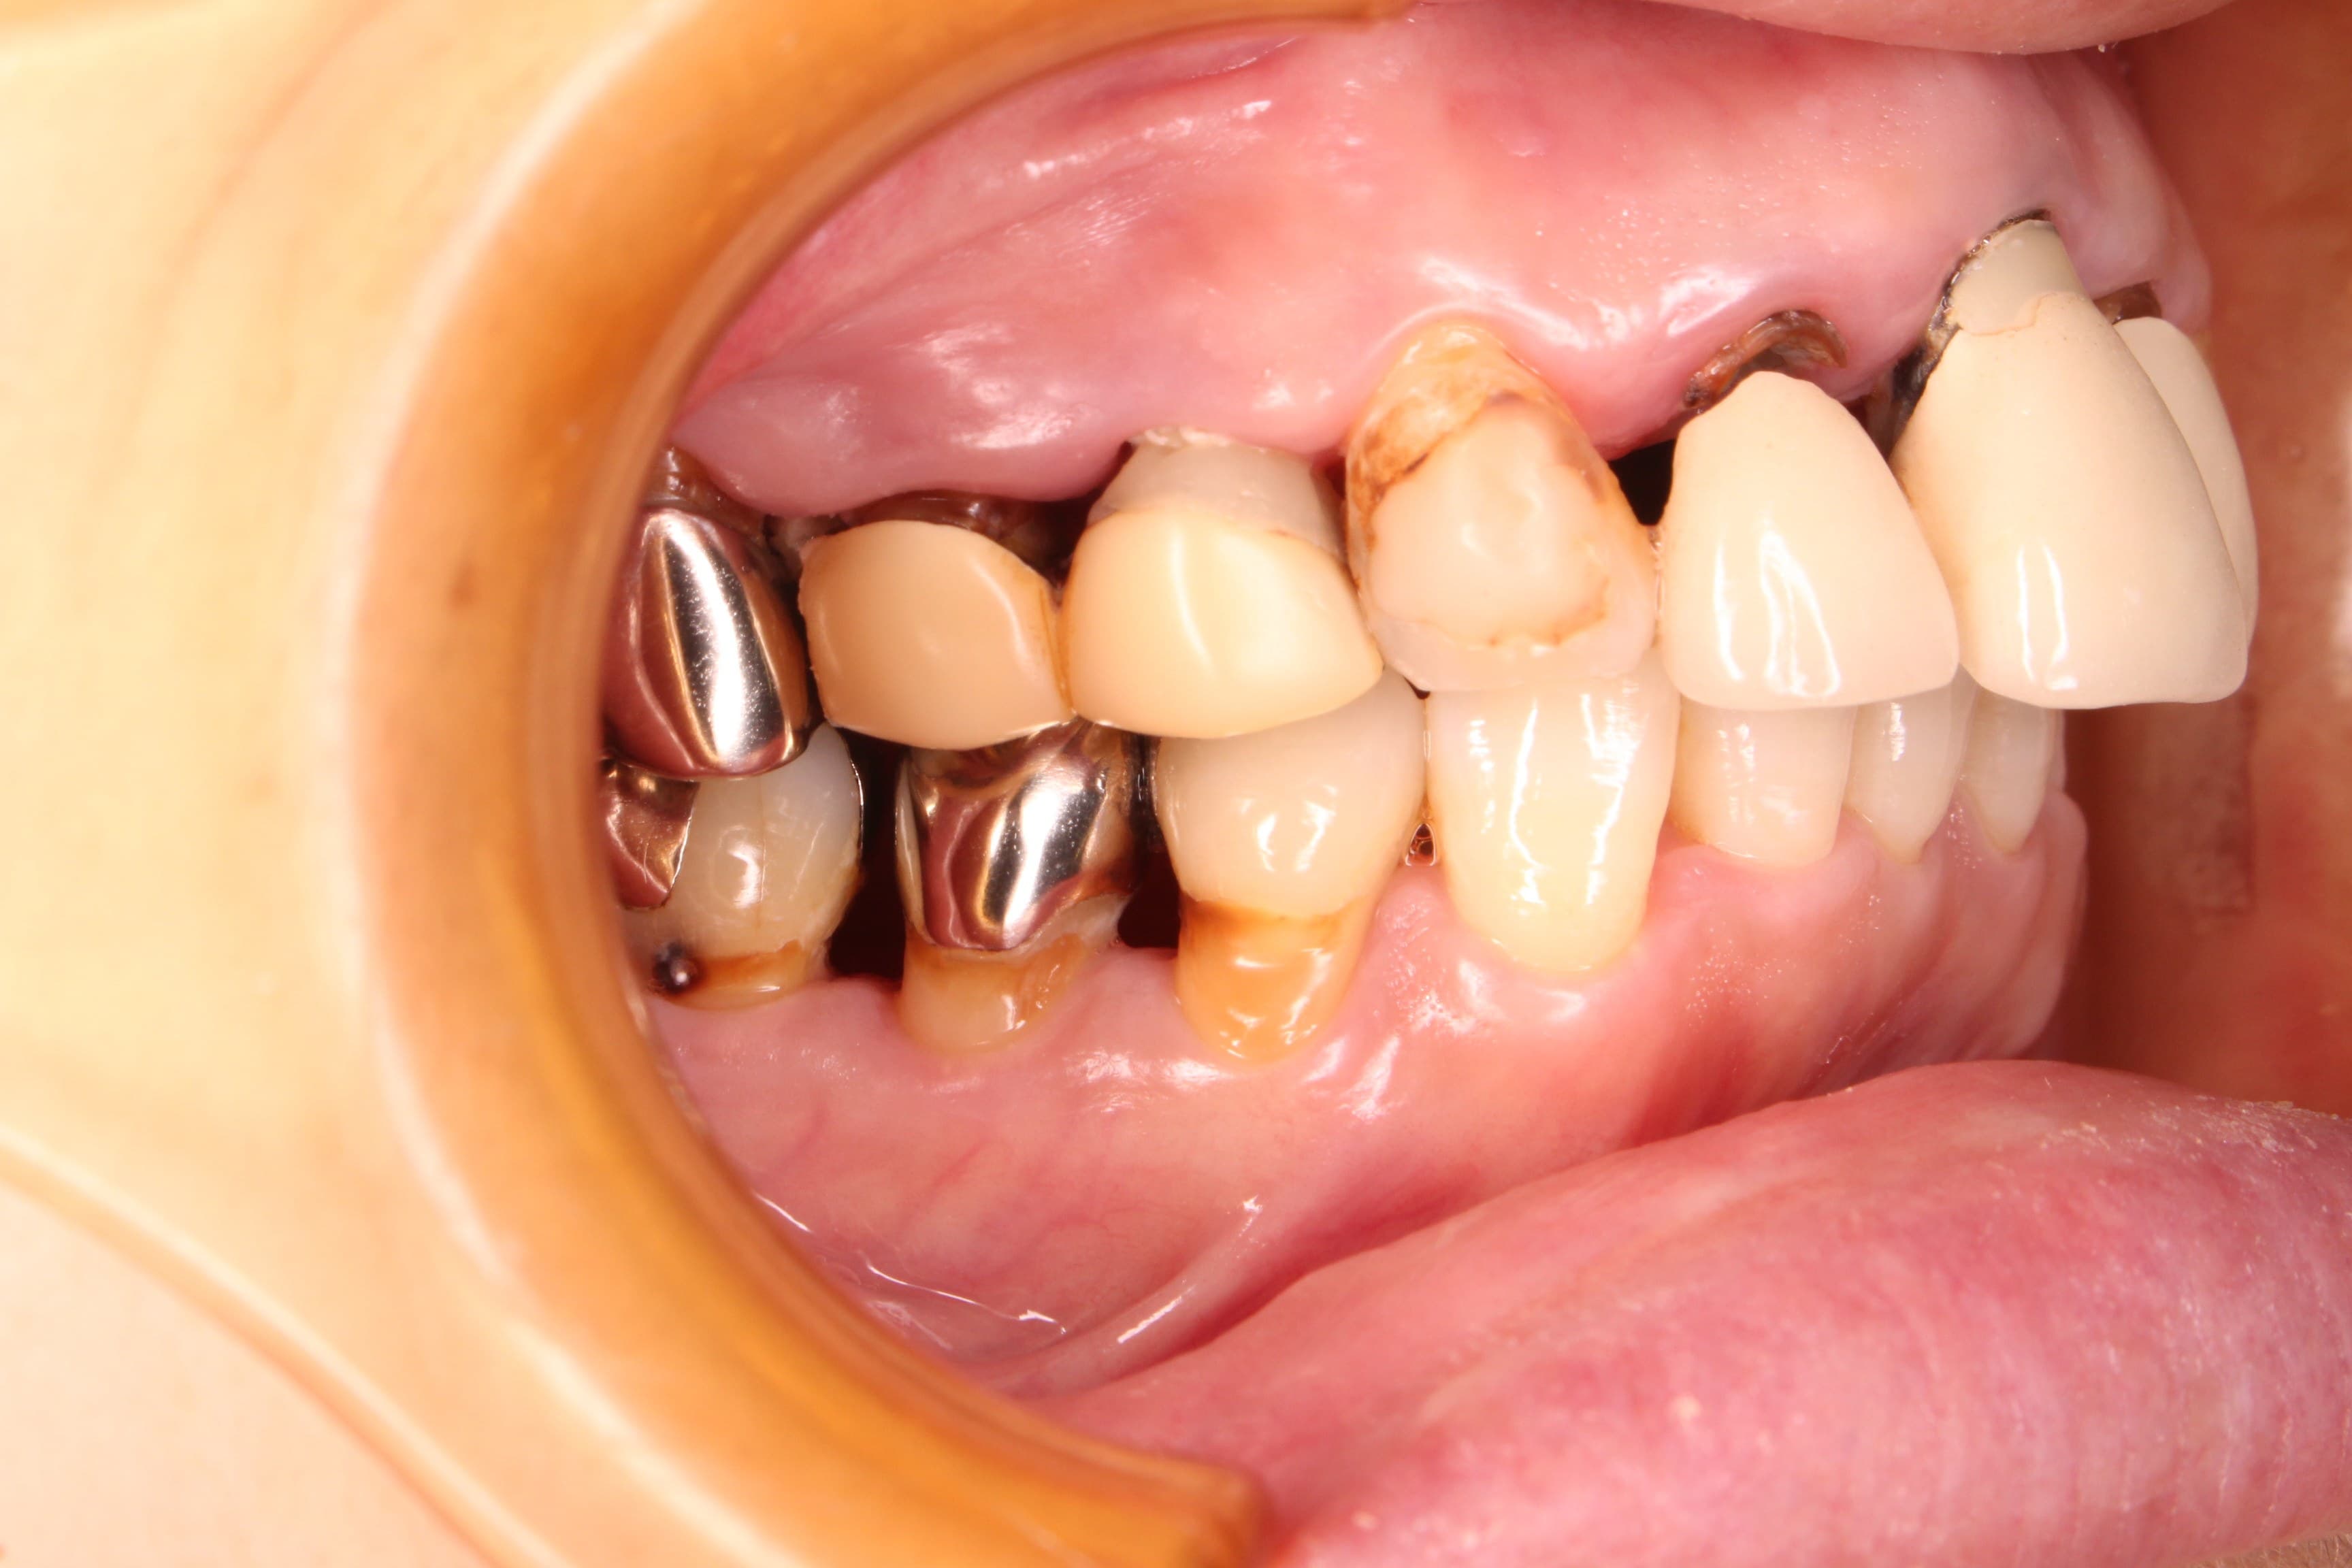

口腔内の状態は、虫歯も大きく進行し、歯周病のコントロールもされておらず、出血やプラーク、歯石等の感染物質も大量に付着していた為、虫歯の治療ができる状態ではありませんでした。

虫歯の治療はこれからですが、ブラッシングの精度もかなり高くなり、虫歯や歯周病に対する予防の知識もしっかりと習得して頂く事ができました。